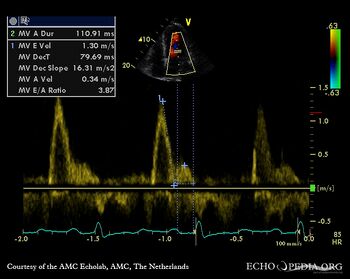

| HCM, diastolic dysfunction

| Courtesy of: AMC Echolab, AMC, The Netherlands

| Pulsed-wave doppler signal of transmitral flow: restrictive flow pattern